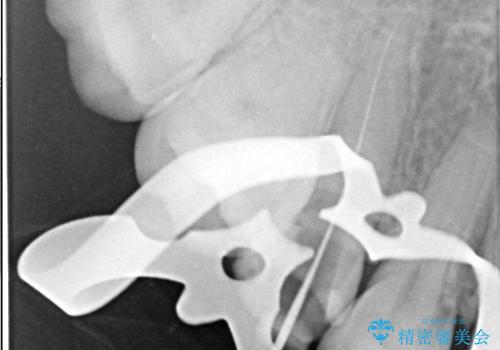

右上5番レントゲン写真上では根管が確認しずらく、根管の狭窄が予想されました。マイクロスコープを使用し、根尖部まで器具を到達させ十分根管洗浄を行うことができました。